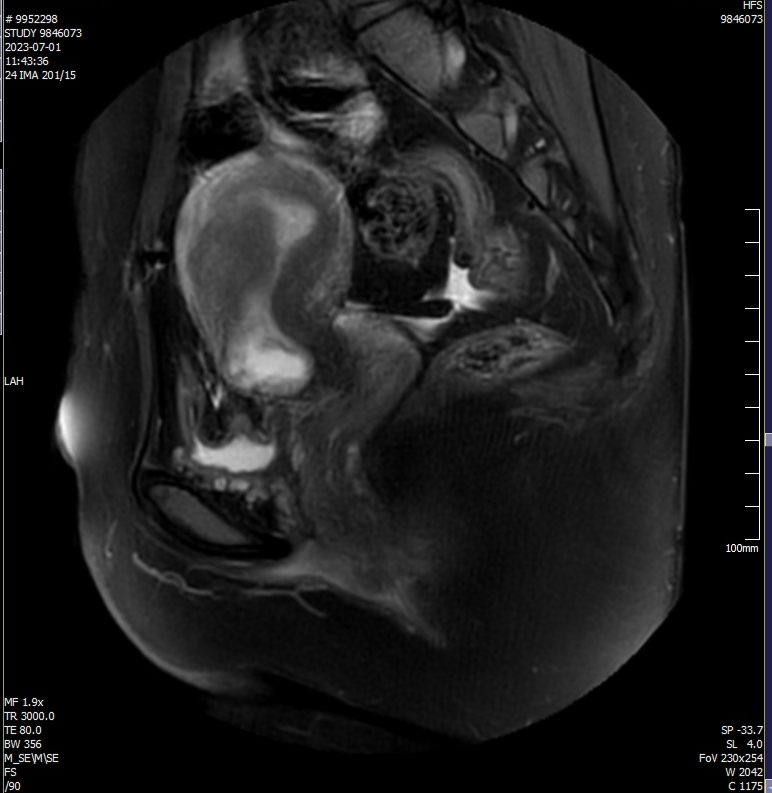

✦当超声检查无法明确妊娠囊与子宫及其周围器官的关系时,可进行MRI检查。MRI检查矢状面及横断面的T1、T2加权连续扫描均能清晰地显示子宫前壁下段内的妊娠囊与子宫及其周围器官的关系。

病史简介

患者,女,30岁,停经40余天,发现瘢痕妊娠1天。

平素月经规律,初潮13岁,6/28-30天,量中,色暗红,白带正常。LMP:2023年5月20日。

G5P2,于2016年、2020年分别行剖宫产1次,2021、2022年分别因个人意愿行药流1次。

辅助检查:

外院2023-6-29行B超提示:瘢痕妊娠6周,妊囊距肌瘤位置较近;宫内实质性占位,考虑肌瘤;左侧卵巢内等回声,建议随诊。

诊断:子宫瘢痕妊娠Ⅱ型

治疗:腹腔镜下子宫瘢痕切除术